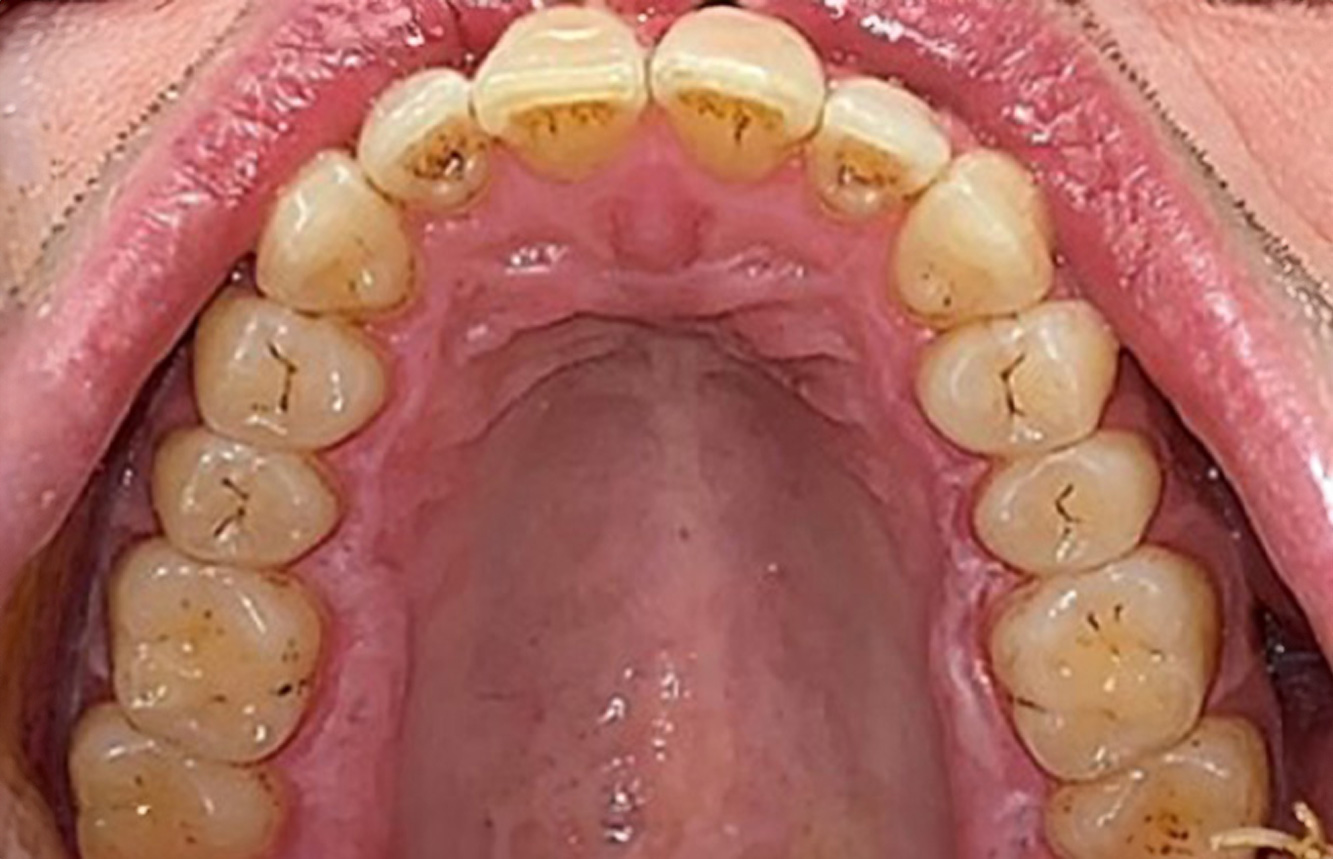

Următoarele studii de caz* acestea au rolul să ilustreze interacțiunea dintre necesitățile și factorii de risc definiți pentru IPC, precum și efectele factorilor individuali.

Pacient transplantat cu proliferări gingivale

Un pacient în vârstă de 71 de ani, cu transplant de rinichi și istoric de hipertonie (hipertensiune arterială) se prezintă în cabinet. Din cauza istoricului său medical, este necesară o medicație pe termen lung cu ciclosporină, pentru a suprima sistemul imunitar, precum și amlodipină pentru a reduce tensiunea arterială. Pacientul raportează, de asemenea, gingii sensibile și sângerânde. Din punct de vedere al sănătății orale, pacientul are lucrări dentare, o edentație de opt dinți, creștere gingivală pronunțată și parodontoză de gradul B, stadiul II, cu pungi active și carii radiculare inițiale la dintele 22. Evaluarea riscului de carie determină un risc moderat de carie (API 60). Se pot stabili următoarele recomandări de tratament pentru ședința de profilaxie. mai multe